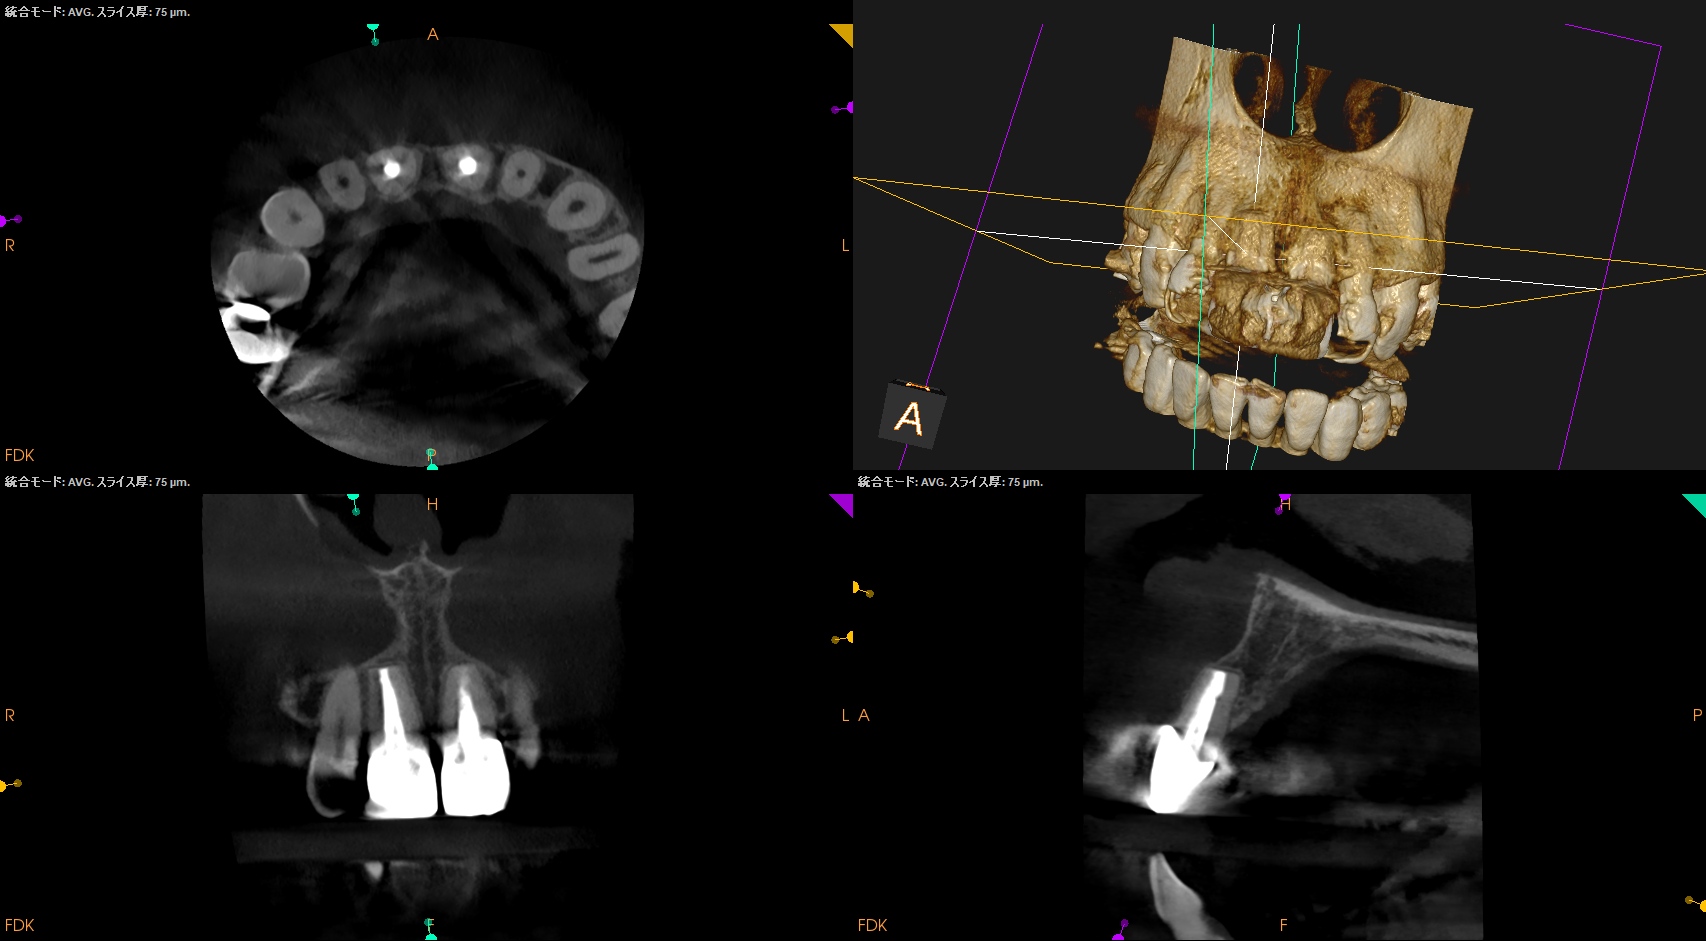

前歯の根元に膿が溜まっていると言われ、抜歯が必要と言われたが抜きたくない。残せないだろうか?〜#8,9 Apicoectomy

#8は通常通り3mm,

#9は歯根の外部吸収があるため臨在歯を考慮しApexから1mmのみ切断して行ったApicoectomy

から1年が経過した。

#8,9 Apicoectomy 1yr recall(2025.10.8)

術後と比較した。

術前の問題は消失した。

#9はやはり術前の予想通り1mmの切断で事足りた。

最終補綴も装着されていることから、この日で終診でいいだろう。